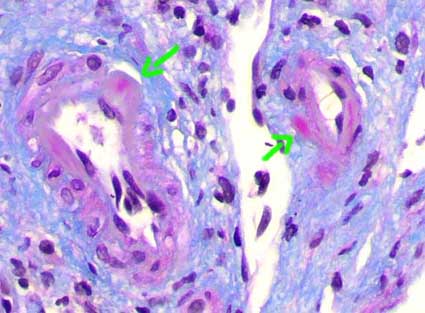

Lesiones arteriales de rechazo crónico: Consisten en proliferación fibrosa de la íntima con células inflamatoria mononucleares en ella: principalmente linfocitos, monocitos e histiocitos vacuolados; hay disrupción de la íntima, mejor apreciada con tinciones para elástico. Encontraremos también proliferación de células miointimales y formación de una segunda "neoíntima". De todos estos hallazgos el más sugerente de rechazo es la presencia de células inflamatorias en la íntima fibrótica.

Figura 16. En el rechazo crónico hay fibrosis intimal acompañada de células inflamatorias mononucleadas e histiocitos espumosos (en algunos casos) (flechas). Hay fragmentación de la lámina elástica interna y disminución de la luz arterial. (H&E, X300).

Figura 17. Con las tinciones para tejido elástico se evidencian mejor las áreas de fragmentación de la elástica interna, un buen indicador de lesión inflamatoria intimal. Observe también la presencia de linfocitos en la intima engrosada. y de ragudo. (Tinción para elástico, X300).